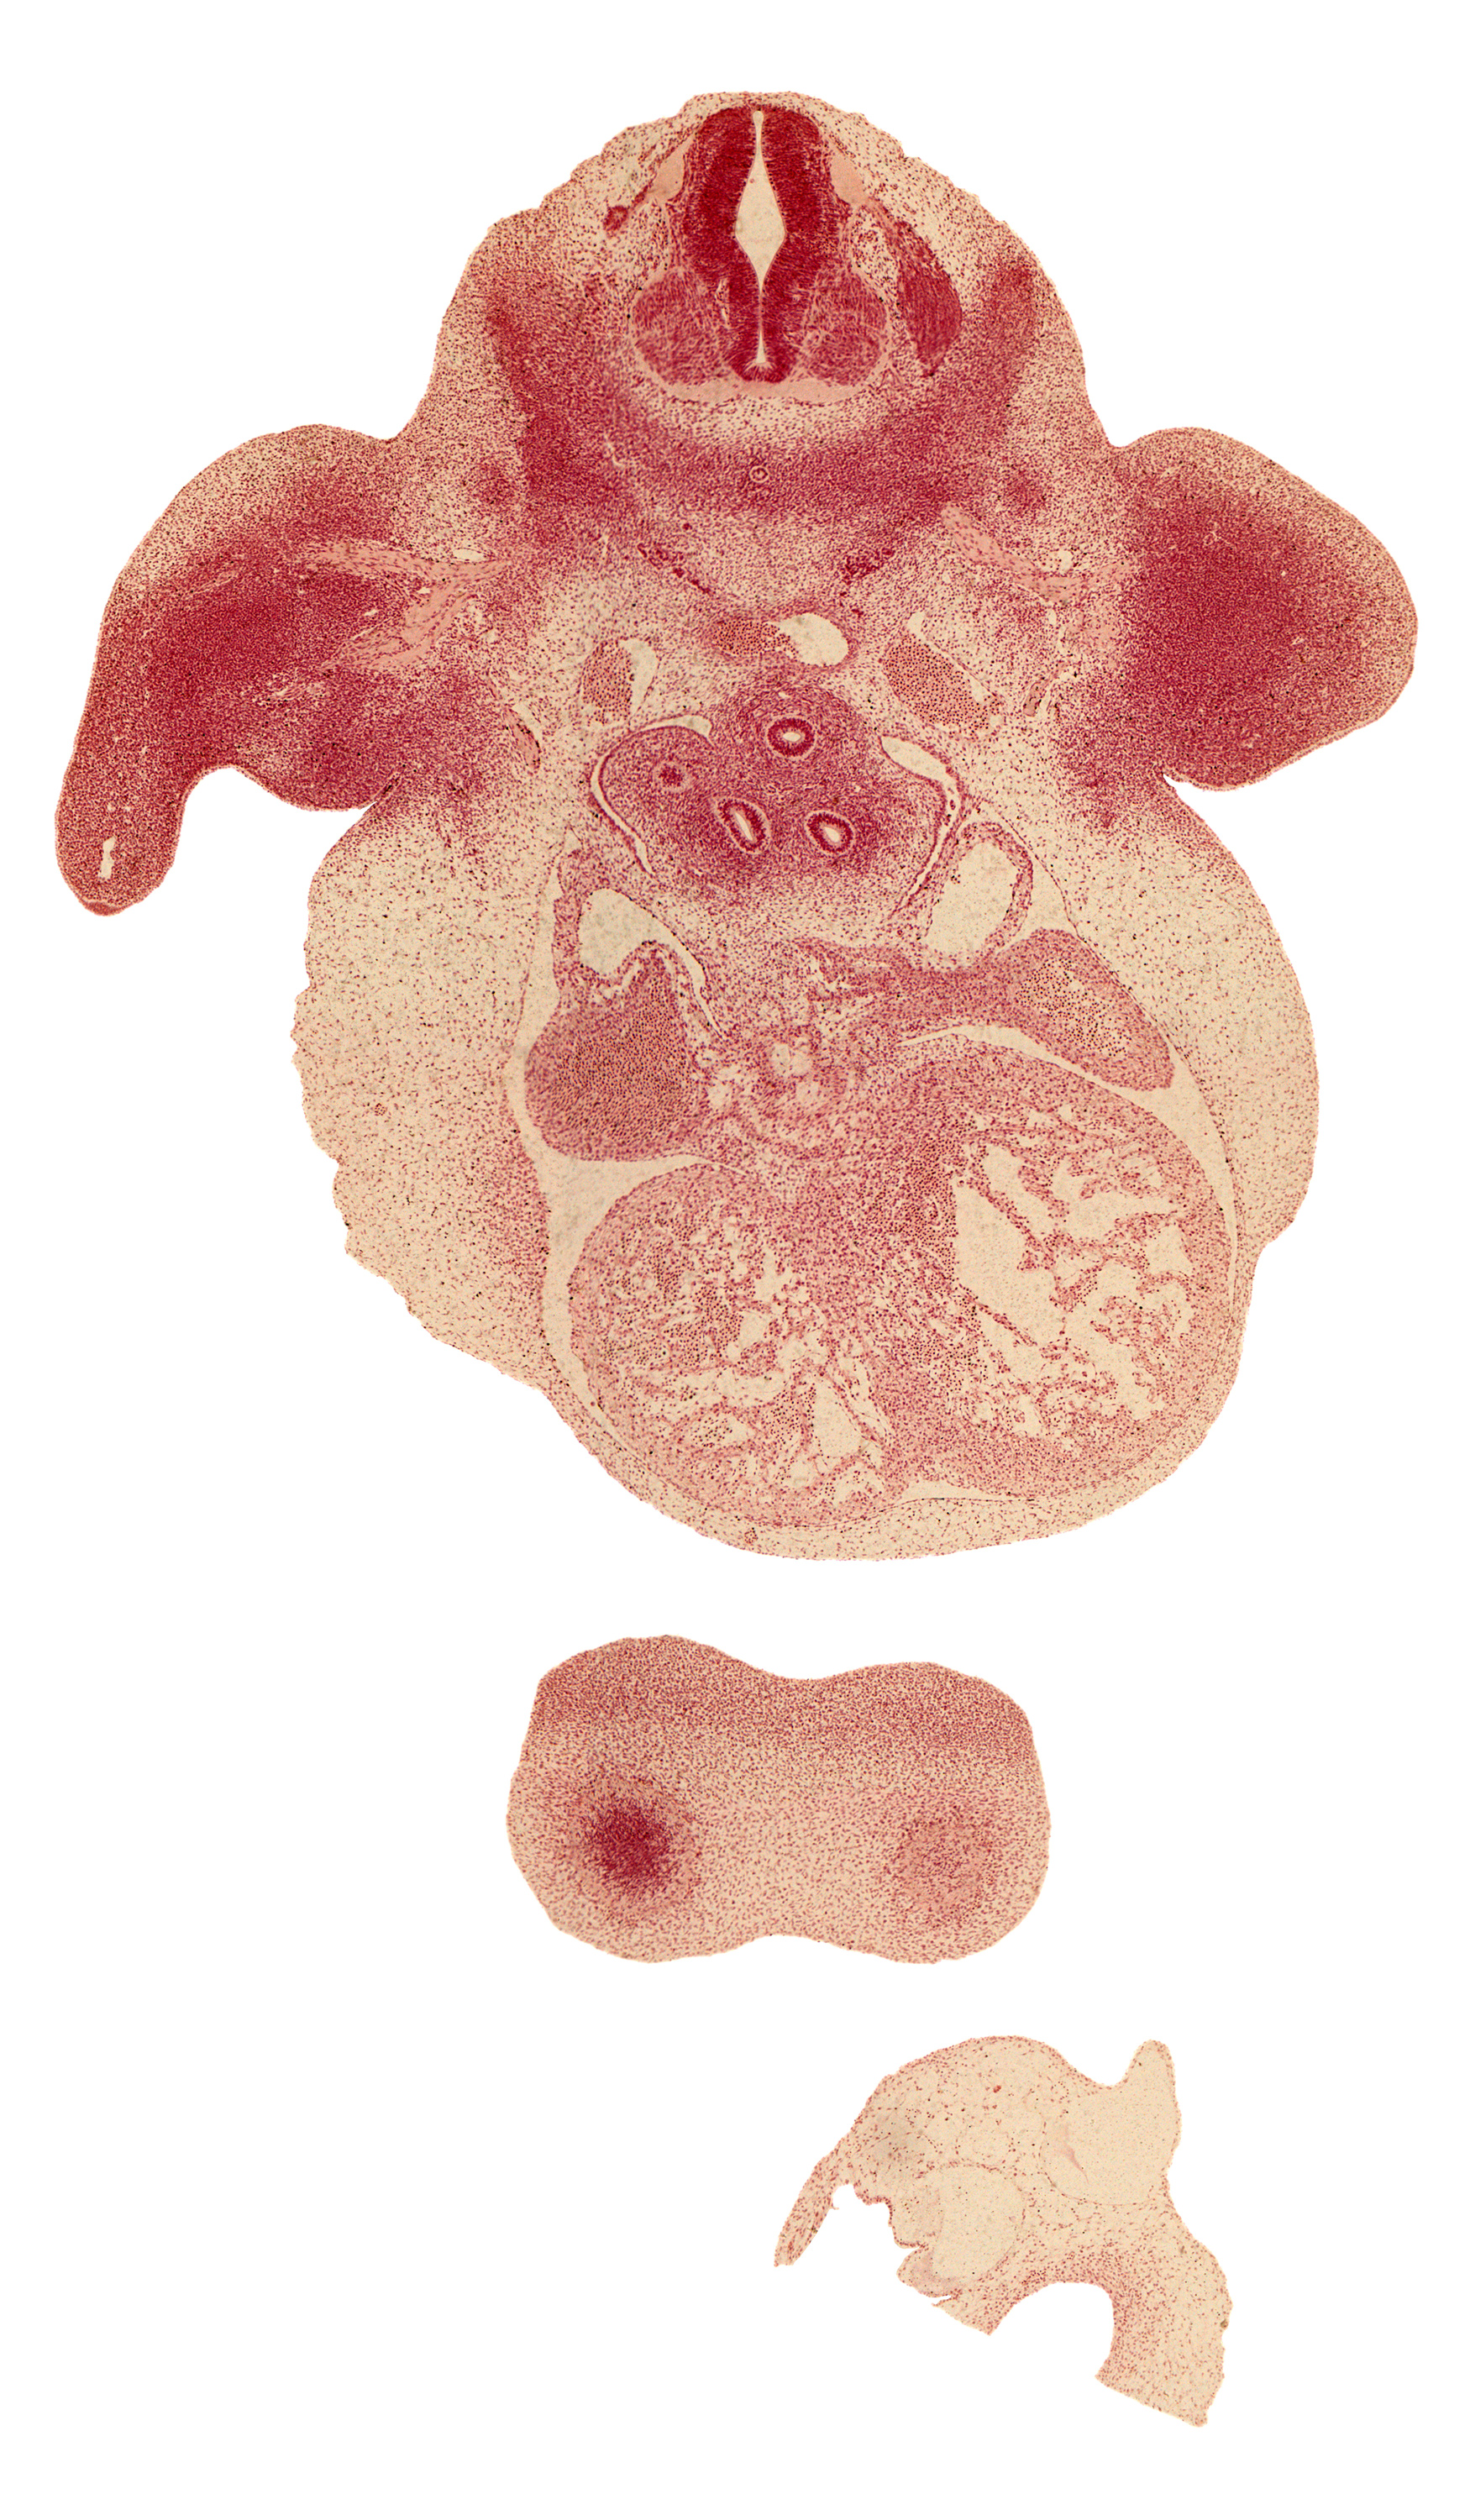

Carnegie Embryo #6517 | Location: 23-01-01

Keywords: C-6 spinal ganglion, anterior spinal artery, cerebral vesicle (telencephalon), common pulmonary vein, edge of upper secondary bronchus bud, esophagus, frontal prominence, hand plate, heart prominence, left atrium, left common cardinal vein, left lung sac, marginal zone, pleuropericardial membrane, postcardinal vein, right atrium, right lung sac, sinus venosus, sympathetic trunk, trabecular part of left ventricle, ventricular zone

Source: The Virtual Human Embryo.